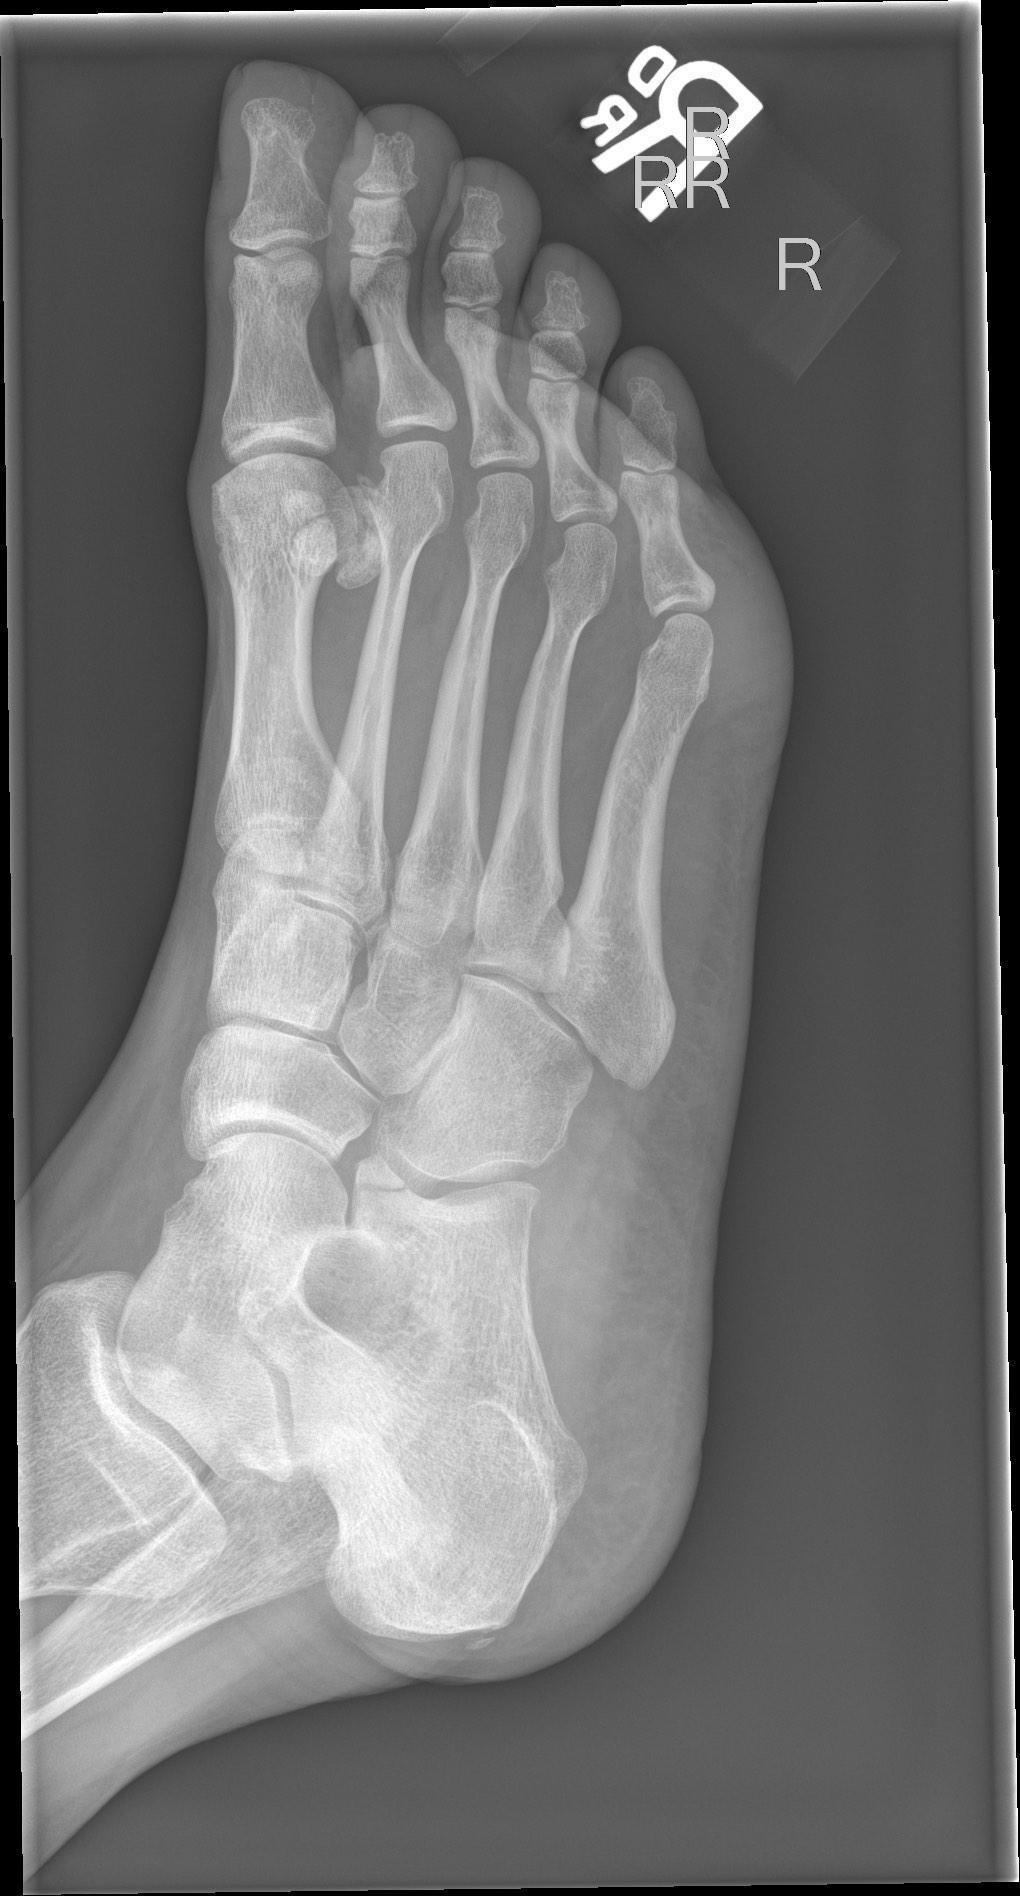

Dai Roberts, Radiopaedia.org. From the case rID: 77584

L’articulation de Chopart met en relation les os du tarse postérieur, c’est-à-dire le calcanéus et le talus, avec respectivement le cuboïde et l’os naviculaire.

Radiologiquement : présence d’un arrachement capsulaire (se traduit par un diastasis) entre le talus et l’os naviculaire ou entre le calcanéus et le cuboïde. On remarque également souvent une fracture associée du 5° métatarsien.